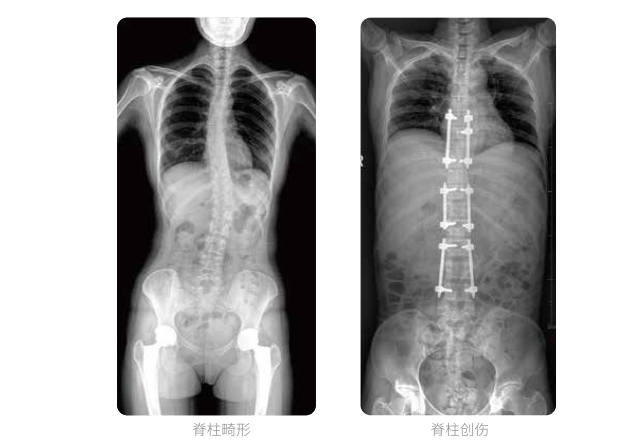

全脊柱臨床影像

普愛醫(yī)療動(dòng)態(tài)數(shù)字化X線攝影(動(dòng)態(tài)DR)可以使整個(gè)脊柱一次成像,直觀顯示脊柱的整體形態(tài)以及側(cè)彎部位,評(píng)價(jià)側(cè)彎的病理程度,全面了解脊柱各個(gè)階段的生理曲度及椎間關(guān)節(jié)連接的關(guān)系,避免了常規(guī)脊柱攝影對(duì)整個(gè)脊柱曲度的影響。為脊柱側(cè)彎的診斷治療提供了重要的影像學(xué)依據(jù)。